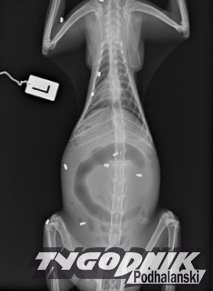

Piętnaście śrutów utkwiło w ciele bezdomnego kota w Brzegach. Za wskazanie sprawcy czeka nagroda.

Jego stan się nie polepszał. Następnego dnia zawiozła go więc do Gerarda Wolskiego, a ten do Lecznicy Weterynaryjnej Luxvet24 w Krakowie. Tam po prześwietleniu okazało się, że ma w różnych częściach ciała aż 15 kul. - Widać tam dwa rodzaje śrutów. Jedne ze zwykłej wiatrówki, drugie nie wiadomo dokładnie z czego. Może to być jakaś broń pneumatyczna lub czarnoprochowa. To broń palna, na którą nie trzeba mieć zezwolenia - podkreśla Gerard Wolski.